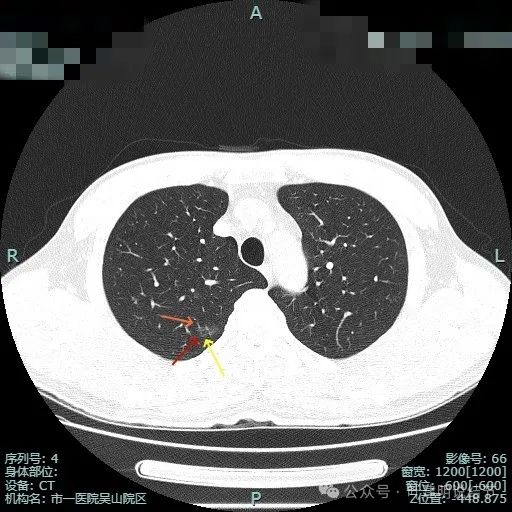

这种样子的混合磨玻璃阴影可直接切肺叶,甚至不必穿刺或活检,太典型了!

病史摘要:主诉发现肺占位半月余,复查胸部CT显示左肺上叶实性类结节影,患者从内科转入,内科已穿刺活检明确为恶性。诊疗过程:体格检查未提及。辅助检查方面,PET-CT 示左上叶尖后段占位,葡萄糖代谢增高,考虑恶性病变可能性大。影像显示病灶为混合密度,有胸膜牵拉、血管增粗等典型浸润性癌表现。杭州市第一

肺腺癌

高度分化癌